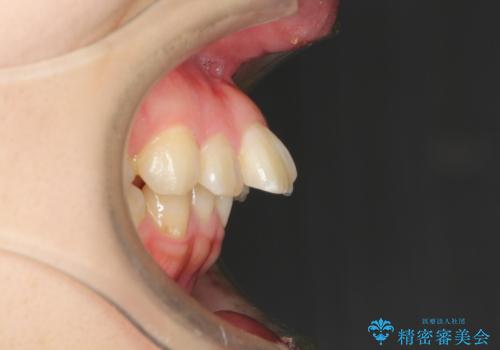

- 口元の閉じにくさと、前歯のでこぼこの歯並びを気にして来院された患者様です。

口元を積極的に引っ込めるために、上下左右の小臼歯計4本を抜歯することとしました。

咬み合わせが深く、咬合力強いため、補助装置を使用しながら積極的に口元を下げることとしました。